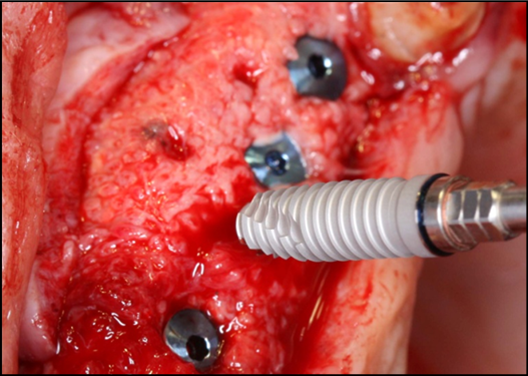

At the 8-months follow-up, a CBCT scan showed consolidation of the grafted material with the recipient bone (Figure 6). A second surgical procedure was conducted under local anesthesia and oral sedation in order to remove the titanium mesh. At this appointment, the pre-maxilla showed to be significantly augmented (Figure 7) with the dimension of 14 mm in height and 10 mm in width. The bone characteristics were soft, erythematous, with a cancellous texture. Four dental implants (Biomet 3I certain®, USA) were inserted, with no more than 25 Ncm2 of primary stability (Figure 8). The implants were uncovered 6 months later for initiation of the prosthetic rehabilitation using 4 single-unit crowns. One-year follow-up showed to be uneventful (Figure 9).

Figure 8.Perspective view of the augmented pre-maxilla with implants(Biomet 3I certain®, USA) #7, 9, 10placed. and #8 beingplaced.